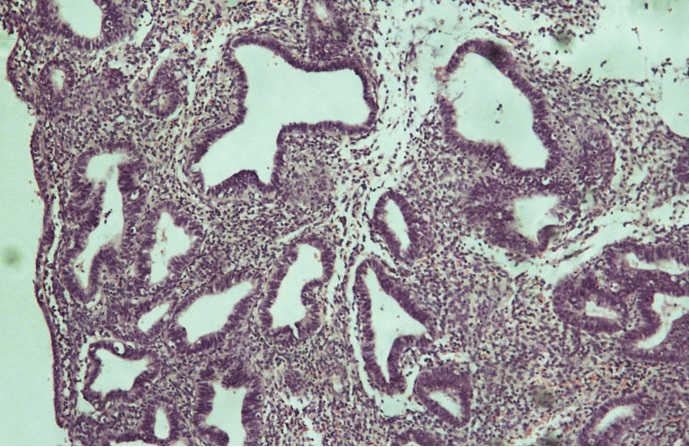

Se presenta el caso de una paciente de 23 años de edad, previamente sana, G1P0A1, con cuadro clínico de hemorragia uterina anormal, a quien se le realizó ecografía transvaginal que reportó embarazo molar, sin embargo tras realizar la medición sérica de B-HCG, fue de 0.00 mUI/ml, por lo que requirió realización de legrado y biopsia para establecer diagnóstico histológico. El resultado evidenció hiperplasia simple, con complejo focal y sin atipia. Se destaca la importancia de la comunicación de este caso, debido a que a esta edad, la presentación de esta patología es infrecuente. Se hace una revisión de los artículos publicados en los últimos 10 años en las bases de datos Medline vía PubMed, y en LILACS en español, inglés y francés. Se tuvo como referencia además textos clásicos.

La hiperplasia endometrial simple en pacientes menores de 30 años es poco frecuente, se debe tener en cuenta la presencia de atipias en la histología pues de ser positivo, es mayor el riesgo de transformación maligna.